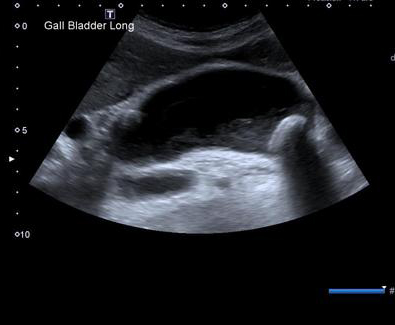

Cholecystite aigue

lithiasique : Images echographique de calcul

vesiculaire avec cone de hypoascoustique posterieure

. Distendue de la vesicule biliaire et epaissisement

de sa paroi . La contenue de la vesicule est

irreguliee . |

Image echographique de

cholecystite aigue lithiasique : Vesicule est

distendue , paroi epais , image de calcul

multiple au ventre de la vesicule biliaire |